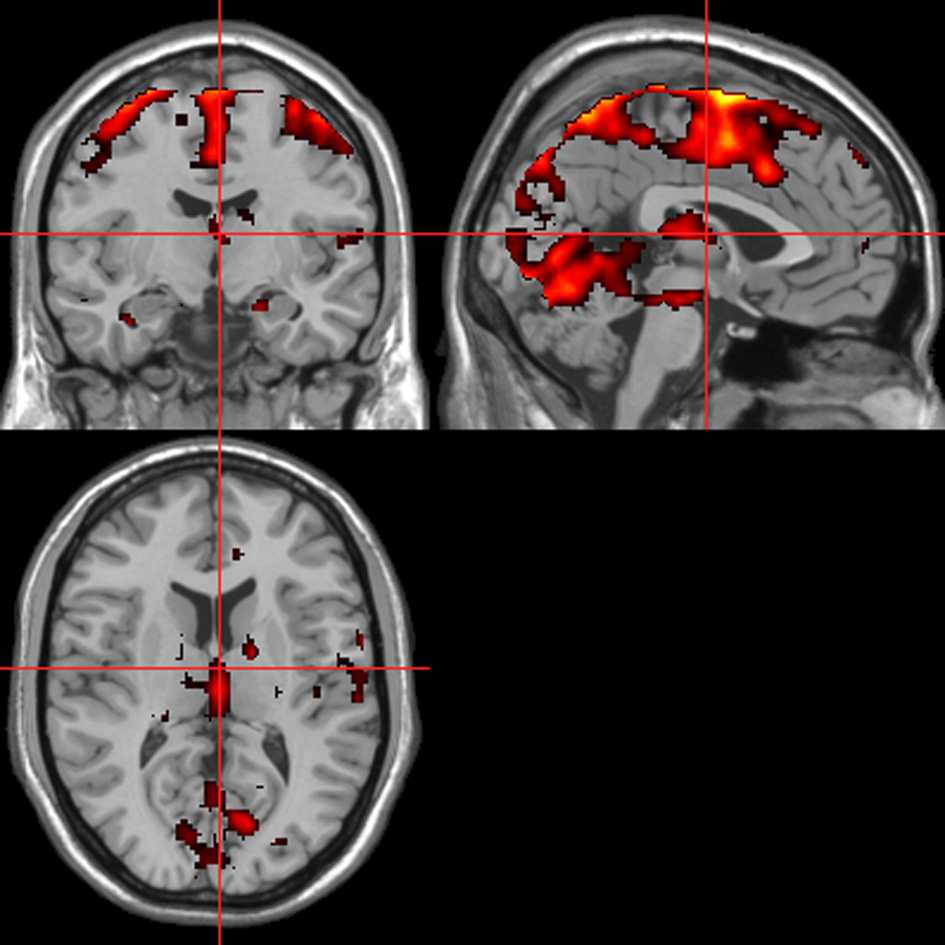

fMRI—autonomic (ISCR) regressor

Across all stimuli (i.e., without differentiating between modalities), ISCR was associated with activations including bilateral precentral gyrus/supplementary motor area [SMA; Brodmann's Area (BA) 4/6], medial prefrontal cortex (mPFC; BA 8), precuneus/cuneus (BA 7/19), thalamus [dorso-medial (DM) nucleus], bilateral lingual gyrus (BA 18) and cerebellum (Table 1; Figure 5; p < 0.05 FWE). Separately, for picture, sentence and sound stimuli, this dorsal (precentral gyrus/SMA) and posterior (lingual gyrus/cerebellum) activation was replicated, though the DM-thalamic activation was only present for picture and sentence stimuli (i.e., not sounds). However, sound-stimuli ISCR data were associated with activation of left amygdala.

Figure 5

ISCR regressor across picture, sentence, and sound stimuli. Main effect of autonomic arousal. Flexible factorial design. p < 0.05 corrected for family-wise error (FWE). Extent threshold = 10. See Table 1 for anatomical descriptions and co-ordinates.